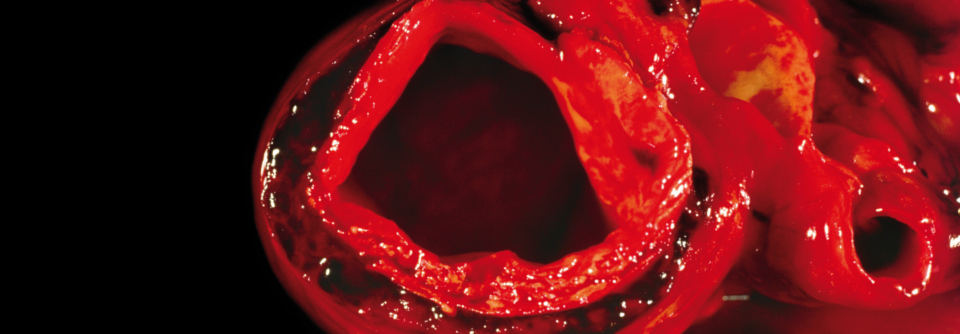

Nicht immer treten die für eine Aortendissektion typischen Zeichen auf. 1: Aorta descendens mit Dissektion. 2: Aortenisthmus. Nicht immer treten die für eine Aortendissektion typischen Zeichen auf. 1: Aorta descendens mit Dissektion. 2: Aortenisthmus. © wikimedia/Dr. Lars Grenacher (CC BY-SA 3.0)